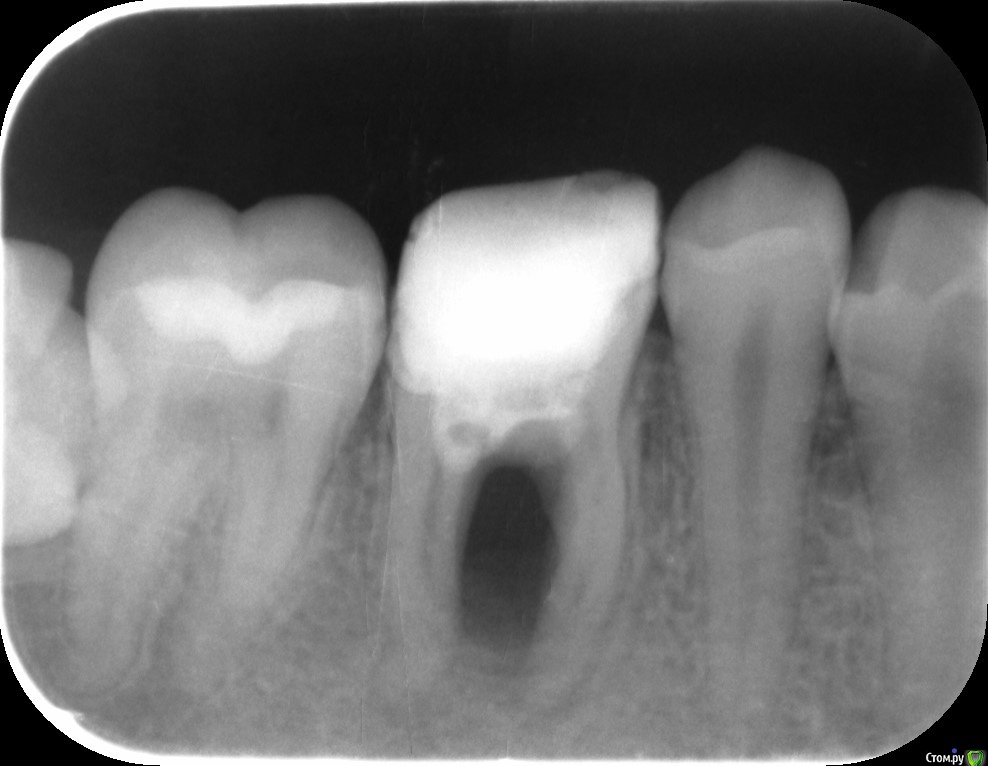

evgflying Опубликовано 21 октября, 2020 Поделиться Опубликовано 21 октября, 2020 (изменено) Добрый день. Пару лет назад лечил этот зуб, врач вылечил плохо, каналы не запломбировал. Об этом я не подозревал. Некоторое время назад распухла щека, обратился к врачу, говорит что нужно удалять. Есть ли шанс спасти зуб? Изменено 21 октября, 2020 пользователем evgflying Ссылка на комментарий

St. Опубликовано 21 октября, 2020 Поделиться Опубликовано 21 октября, 2020 Добрый день. Шанс на успех очень маленький, есть риск что в месте где расходятся корни зуб разрушен.И, кстати, зуб мудрости с этой стороны упирается в соседа и может его испортить Ссылка на комментарий